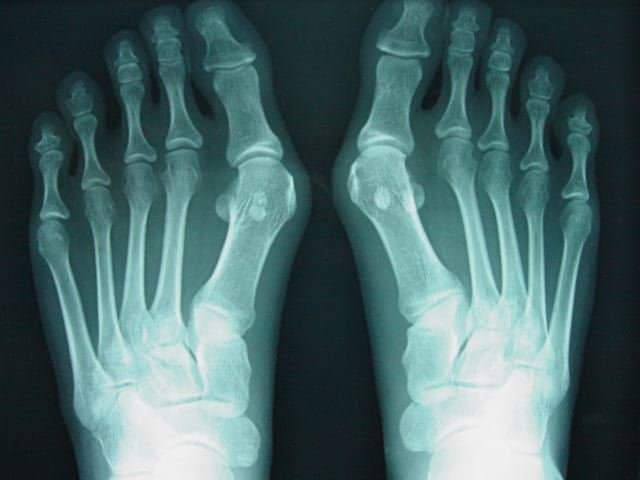

外反母趾は、母趾が「くの字」に曲がって、出っ張ったところが当たって痛くなる病気…

と言われていますが・・・

先天性の遺伝要因や後天性の足の怪我や履物の影響により、足が持つアーチバランスが徐々に崩れてしまい、足の筋肉の中でも特に母趾外転筋を中心とした母趾に関係する筋肉が変形の進行と共に「歩く際に使えなくなる」病気だと思っています🤔